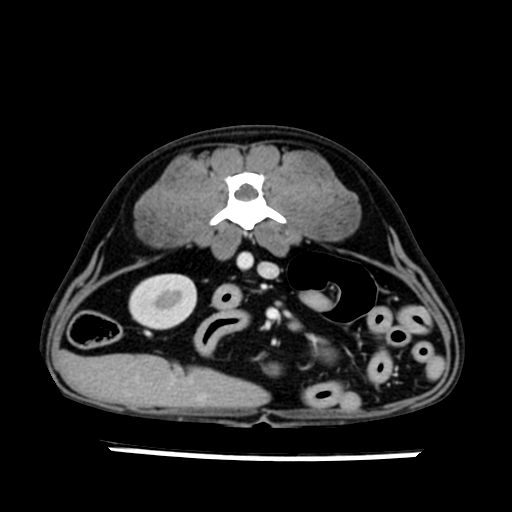

prescritto esame TAC

sequenza immagini limitata al fegato reni e surreni

le immagini ecografiche rispetto alla tac datano circa 7 mesi prima ,le surrenali sono normali nonostante il test acth sia risultato positivo .all’esame TAC dopo diversi mesi risultano aumentate armonicamente nel volume e si individua un forte sospetto di adenoma ipofisario .

sospetto adenoma ipofisario vs. meno probabilmente meningioma della base; intertiziopatia polmonare; lesione espansiva epatica, verosimilmente del lobo laterale sinistro, di sospetta natura neoplastica; lesioni spleniche di natura da definire; iperplasia/ipertrofia delle ghiandole surrenali, bilateralmente; vertebra di transizione del rachide toracico; tenosinovite cronica del muscolo bicipite brachiale di destra.

- Nessuna informazione diversa per quello che riguarda l’esame ecografico del fegato e la presa del contrasto si confermano le lesioni individuate e l’ipoenanchement in fase portale.

- la total body permette di escludere metastasi e di avvicinarsi all’interventistica

la tac dopo 7 mesi permette misure tridimensionali 5,2 x 9,2 x 4,5 cm (forma piu’ allungata )